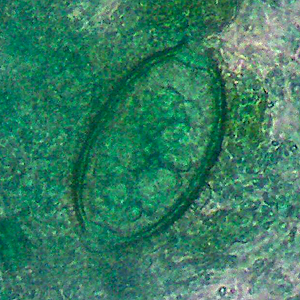

A 26-year-old female presented at a local hospital with severe pain and bloody discharge from the ear. The symptoms started while on a returning flight from vacation in Central America. The patient explained that while on vacation she visited a local physician to have a fly removed from her ear canal.